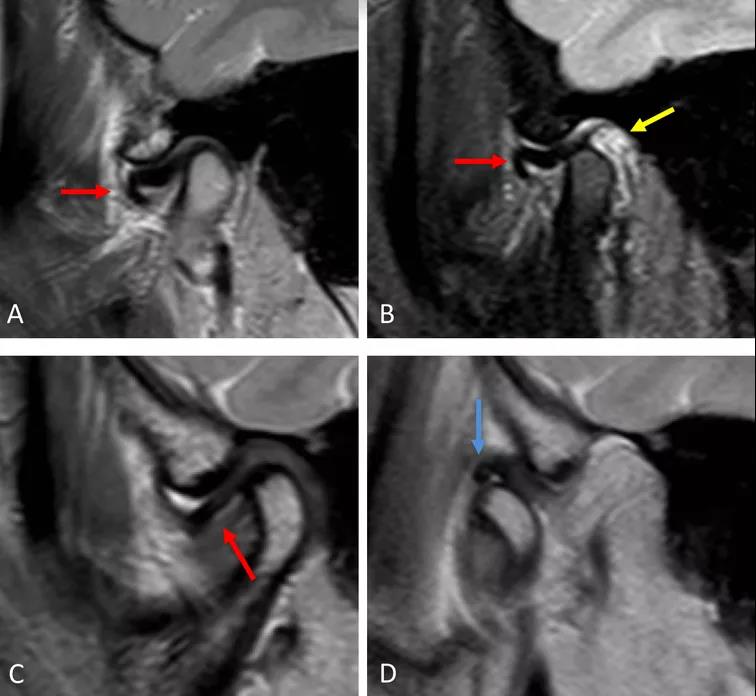

病例一:斜矢狀平面上的質(zhì)子密度加權(quán)圖像(PDWI)

A圖示:閉口位時,顯示關(guān)節(jié)盤前移位明顯,雙凹形態(tài)消失。注意前帶的下移位(紅色箭頭)。

B圖示:張口位時,顯示關(guān)節(jié)盤移位(紅色箭頭),關(guān)節(jié)積液(黃色箭頭)。病例2:斜矢狀平面上的質(zhì)子密度加權(quán)圖像(PDWI)

A圖示:閉口位時,顯示下頜骨髁突前上側(cè)面硬化,前方扁平的椎間盤移位(紅色箭頭)。